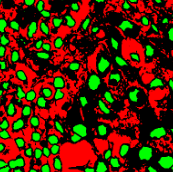

Point annotation can be viewed as the most efficient manner for annotation, gaining increasing attention in cell/nuclei segmentation. Existing methods [23, 24, 25, 26] mainly encode the point annotation into coarse pixel-level labels, such as point distance maps [23], Voronoi labels [24], cluster labels [25], and pseudo edge maps [26]. As shown in Fig. 1, these methods typically inject the shape and texture prior knowledge of nuclei into coarse pixel-level label. For example, the points are assumed to be around the center and the nuclei shapes are nearly convex. Despite drastically reducing the annotation cost and alleviating the data-imbalance problem of point annotation, these methods still suffer from incomplete coarse labels and inaccurate boundary information, as illustrated in Fig. 1. Various methods have been proposed to eliminate the distraction induced by the coarse labels, which can be categorized into two classes: 1) multi-stage optimization to refine the segmentation in a bootstrapping way [23, 27, 24]; 2) adding additional constraints based on the local contrast between nuclei and their surrounding cytoplasm [25, 26]. However, the additional constraints could introduce inaccurate supervision, and a multi-stage learning strategy may suffer from error accumulation (i.e., the global optimum cannot be guaranteed).

In practice, directly using point annotation for the nuclei segmentation could suffer from the data-imbalance problem due to insufficient supervision information. To alleviate this issue, we adopt the Voronoi diagram [24] and the -means clustering method [25] to generate Voronoi label and cluster label, respectively. Specifically, for Voronoi labels, as shown in Fig. 1, the image is divided into convex polygons based on the point annotations with the assumptions that the point labels are at the nuclei centers and nuclear shapes are convex (even though these assumptions are not necessarily valid). For cluster labels, as shown in Fig. 1, we utilize the -means to obtain more supervision information of nuclei boundary and shape as follows. First, we calculate the distance maps from the point labels by performing distance transform between each pair of points. Second, the distance maps are combined with the original H&E stained images to conduct the -means clustering to divide all pixels into clusters: nuclei, background, and ignored area. The clusters that have maximum and minimum overlap with the point annotations are labeled as nuclei and background, respectively. The remaining one is the ignored class. The introduction of an ignored area allows pixels that cannot be easily determined as nuclei or background with certainty not be forced into either class, ensuring that the clustering can assign correct pixel labels as much as possible [27]. Third, several morphological operations are adopted to refine the cluster label, including connected domain labeling, scattered region removing, morphological opening operation, and binary hole filling.

where and denote the Voronoi label and cluster label of nuclei at the -th pixel, respectively; denotes the prediction of the segmentation network with H-component as input; and (i.e., or ) is the set of non-ignored pixels. As illustrated in Fig. 1, the Voronoi label is used to supervise the network to separate overlapping nuclei, while the cluster label could provide coarse shape and boundary information for nuclei segmentation. In the following, we elaborate the co-training strategy to further provide supervision to the ignored area of the coarse cluster labels, denoted with the blue color in Fig. 1.

To investigate the impact of the proposed co-training and colorization methods, we validate the effectiveness of each module on the MoNuSeg dataset. Considering that Voronoi labels provide more shape supervision information than point annotation, we regard the model that jointly uses the point annotation and the Voronoi label as the baseline, and mainly evaluate the improvement of each module upon this baseline in Table III. Model A utilizes only point annotation and Voronoi labels with cross-entropy loss. For a fair comparison with co-training, we employ two separate models which have the same architectures for co-training and average the predictions of the two models in inference. Model B further adopts the cluster label. It can be seen that the cluster loss is beneficial in segmenting overlapping nuclei, improving the from 60.20% to 72.48% and the AJI from 43.01% to 51.77%, which indicates that simply using the point annotation and the derived Voronoi labels cannot provide sufficient supervision for the nuclei segmentation due to the lack of boundary and area information. However, the cluster labels generated by the -means algorithm cannot separate close nuclei which would introduce distraction to the training process, as shown in Fig. 1. To address this challenge, Model C utilizes the co-training strategy that the two models facilitate each other in a bootstrapping way to eliminate the distraction brought by the cluster labels. As expected, co-training brings a consistent improvement in all metrics, including an 1.19% increase to AJI. We believe that co-training compensates for the loss of supervision information in the uncertain regions in the cluster label, and the probability map with EMA by another model provides more precise and robust supervision in the nuclei boundary. Visualization of the segmentation results can be found in Fig. 3, and it can be seen that with the co-training strategy, the model can achieve more accurate results, especially in the nuclei boundary area. Model D involves colorization as a proxy task to implicitly learn to be self-aware of the nuclei boundary. Instead of directly coloring the H-component (Fig. 4(a)) to the H&E map (Fig. 4(d)), we use the segmentation probability map (Fig. 4(b)) as the input of the colorization network, which can help us to boost the segmentation accuracy. The experimental result shows that integrating the colorization tasks could not only improve the by 1.54% and AJI by 3.24%, but also promote Acc by 0.18% without dropping F1 score, proving that the colorization task has a significant guiding effect on nuclei segmentation. In Fig. 4(c), the improvement of colorization in the nuclei boundary area can also be observed. In general, the four modules used in our method have complementary advantages. By minimizing the weighted sum of the four losses, the proposed framework can distinguish between nuclear and non-nuclear to the greatest extent.